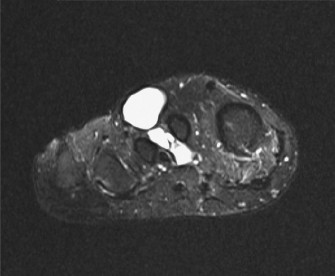

• Magnetic Resonance Imaging (MRI): The gold standard for local staging. It provides detailed information on tumor size, exact anatomical location, relationship to neurovascular bundles, bone, joints, and adjacent soft tissue compartments. T1-weighted, T2-weighted with fat suppression, and post-contrast T1-weighted sequences are typically utilized. MRI helps delineate the extent of peritumoral edema and identify skip lesions.

• ![Image](/media/upload/c37e8e7e-e208-4601-9f5a-cb85e4fa5123.jpg)

Figure 1: Pre-operative MRI depicting a soft tissue mass in the foot/ankle, illustrating its anatomical relationship to surrounding structures. High-resolution imaging is crucial for accurate staging and surgical planning in clear cell sarcoma.